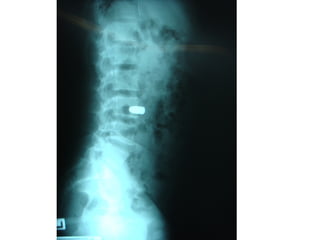

ผู้ป่วยชายไทยอายุ19ปี

CC:ถูกยิงที่คอมา2ชั่วโมง

PI:2ชั่วโมงก่อนผู้ป่วยถูกยิงขณะเดิน

กลับบ้านได้ยินเสียงปืนหลายนัดไม่ทราบ

ระยะยิงกระสุนถูกที่คอด้านซ้ายไหล่ซ้าย

ล้มลงขยับแขนขาไม่ได้ชาทั้งตัวตั้งแต่คอ

ลงไปไม่สามารถพูดได้ญาตินำาส่งถึง

รพ.เอกชน15นาทีหลังเกิดเหตุ

BP 88/56 mmHg, HR 92/min

RR 22/min ,BT 37oC, O2sat 100

SPINE

1. Spinal cord decompression and steroids

2. Remove bullets? Or bony fragment?

3. Associated intra-abdominal injury

4. Spine instability

5. Lead toxicity